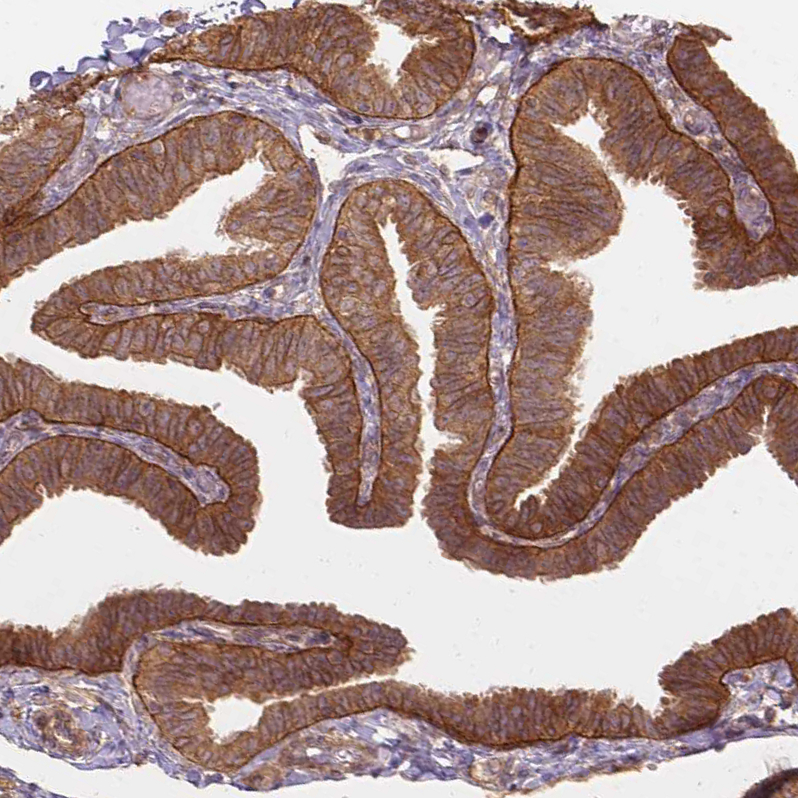

Immunohistochemical staining of human Testis shows strong membranous and cytoplasmic positivity in spermatogonia and cells in seminiferous ducts.